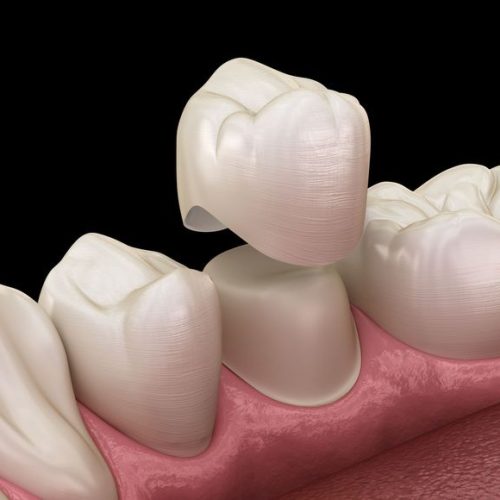

Dr Nitesh Rai, specializes in replacement of teeth with complete dentures, removable partial dentures, fixed partial dentures and Implants.

He is really a humble person and well-qualified in his profession. My experience was amazing. He explained the issue and solutions and also gave me sometime to think on the procedure. I underwent the implant procedure, which was remarkably pain free. After 3 months the teeth was placed . Thanks to his precise digital measurements and meticulous attention in detail . Today , I have a prefect crown in place . I am grateful to Dr Nitesh Rai for his exceptional skill and compassion , for restoring not just my smile but my confidence too.